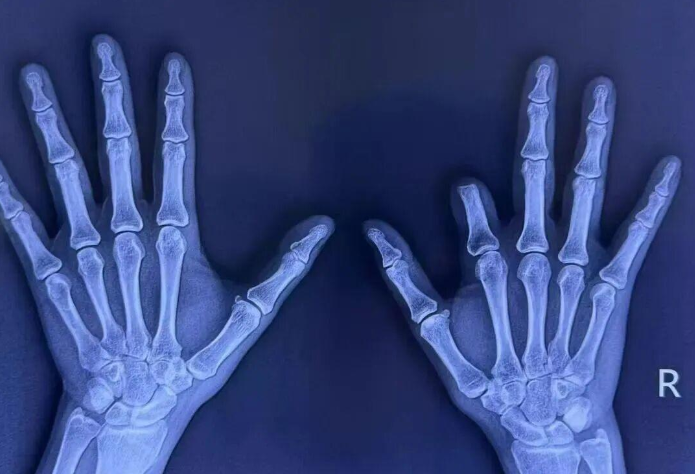

• 毫米間的生命藝術(shù),蓮池骨科高難度手指再造術(shù),為廣東患者重燃希望

來源:大眾新聞·半島新聞半島網(wǎng)9月30日訊 (記者 齊娟 紀(jì)豪杰)因一年前機(jī)器擠壓導(dǎo)致右手示指五度缺損,44 歲的葉女士帶著一份堅(jiān)定的希望,從廣東到山東,跨越千里,來到蓮池骨科尋求治療。修復(fù)重建外科楊志主任團(tuán)隊(duì),創(chuàng)新設(shè)計(jì) “組合式” 再造方案,聯(lián)合多手術(shù)組在40倍顯微鏡下奮戰(zhàn)超22小時,為葉女士重獲手指的功能與自信。千里求醫(yī),希望所寄從廣東到山東,跨越千里,44歲的葉女士帶著一份堅(jiān)定的希望來到蓮池